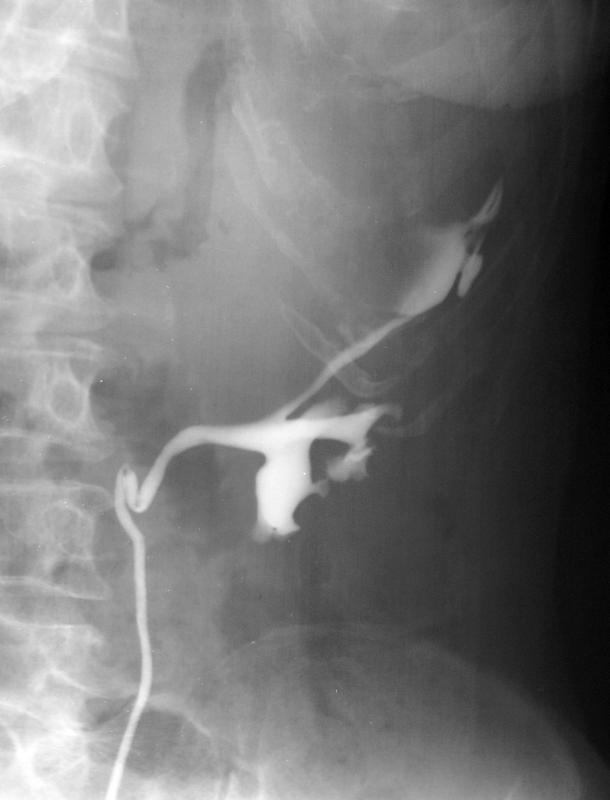

IVU:

Hipernefrom lijevog bubrega